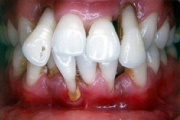

Agressiivse parodontiidi kahjustused rasedal naispatsiendil